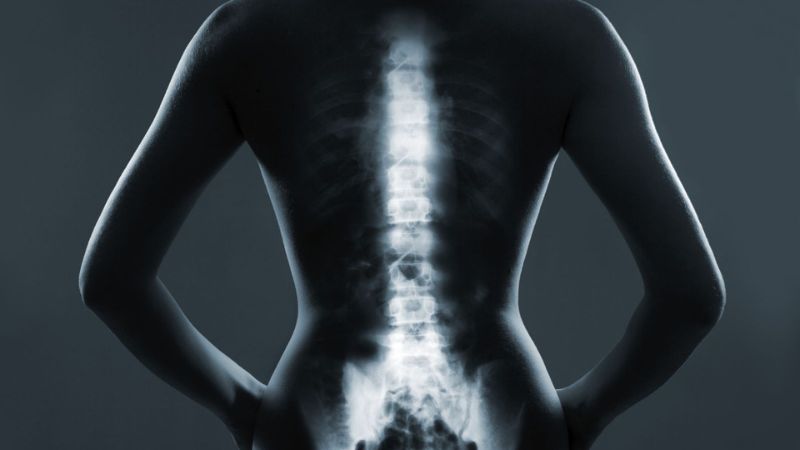

U cột sống thắt lưng là tình trạng xuất hiện một khối mô bất thường tại vùng cột sống thắt lưng – đoạn cuối của cột sống nối với xương cùng. Khối u có thể hình thành bên trong tủy sống hoặc ở khu vực xung quanh ống sống.

- X-quang cột sống giúp phát hiện các biến dạng xương, khối u hoặc tổn thương cấu trúc. Tuy nhiên, phương pháp này không cho bác sĩ thấy rõ mô mềm và tủy sống.